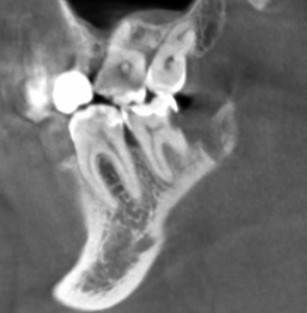

Александр9 Опубликовано 24 ноября, 2021 Автор Поделиться Опубликовано 24 ноября, 2021 спасибо за ответы! Впервые наблюдал за лечением своего зуба на экране. С микроскопом оказалось действительно лучше, т.к. зуб достаточно глубоко был поражен и приходилось тщательно его "вычищать" изнутри. Правда в стенке все же образовалась дырка и пришлось ее заделывать "заплаткой". На снимке видно темные области под временной пломбой. Это не помешает проходить с ней 4 месяца до установки коронки? 1 Ссылка на комментарий

St. Опубликовано 26 ноября, 2021 Поделиться Опубликовано 26 ноября, 2021 По снимку все красиво! Под такой временной пломбой может быть неконтрастный материал или "ваточка". Тем не менее долго ходить с временной пломбой не стоит и чем быстрее Вы попадете на восстановление и коронку тем лучше (меньше риск что отколите остатки стенок и повторного попадения микробов). Кстати, если вдруг временная выпадет, обязательно показаться доктору и вернуть ее на место. без временной ходить категорически нельзя. 1 1 Ссылка на комментарий